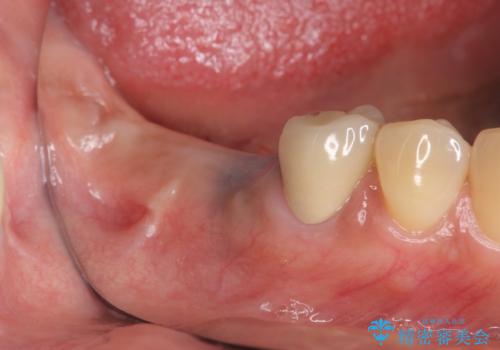

[ 臼歯部インプラント治療 ] 抜けた歯を治療したい

![[ 臼歯部インプラント治療 ] 抜けた歯を治療したいの症例 治療前](https://seimitsushinbi.jp/wp/wp-content/uploads/2022/06/b20681531f81bbbcb107d489675c3fe3-500x350.jpg?v=1655969039)